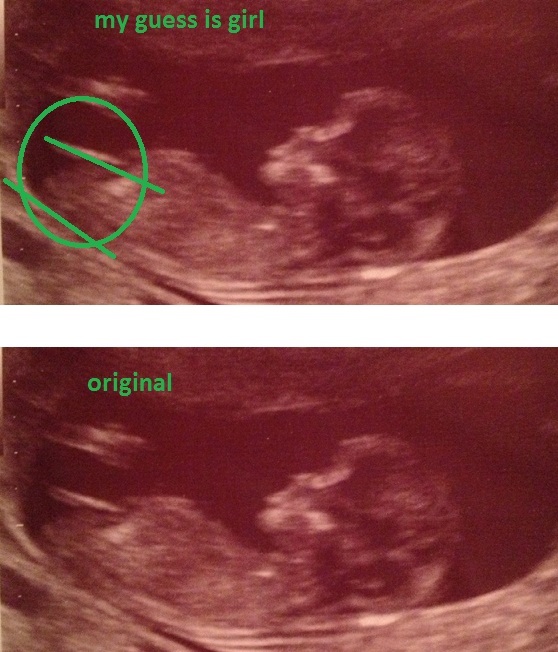

Please guess ladies :) and if you wish, give a reason why you think what you do :) xx

Very girly nub :) Looks like same as my, nub is even pointing a bit down! Do you have any preference?

Classic girl nub. This is what I am hoping to see next week

That is a classic girl nub

I'm pretty sure that's your little girl! Looks extremely girly. So sorry to hear about your little boy. In regards to your baby this time, that's not a leg so don't worry about that. It's the nub and a very girly one at that.